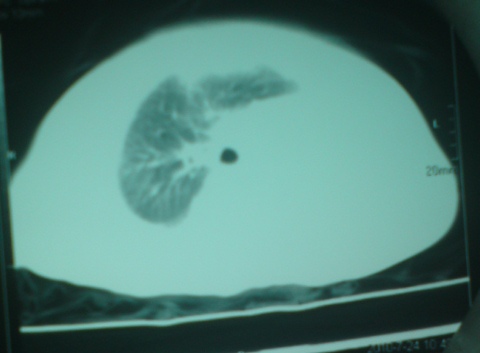

以下是引用liaoqiang在2010-7-26 13:10:00的发言:[br]左侧主支气管未显示,左肺体积明显缩小。右肺体积大。肋间隙不窄。考虑左肺不发育伴右肺代偿性肺气肿、纵隔疝。

以下是引用江广1996在2010-7-26 10:34:00的发言:[br]因为胸廓对称,肋间隙基本正常,故考虑为先天性左肺不发育。[br]如为异物,也会有临床病史。另,这与双胞胎有什么关系,另一个情况怎样?有无检查过?